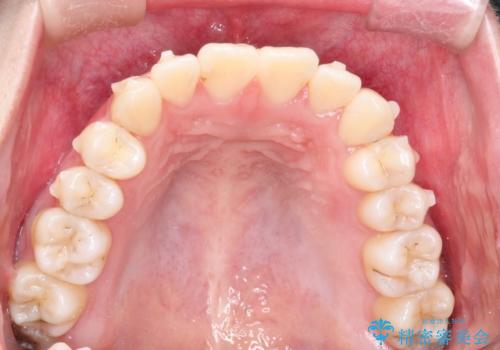

インビザラインによる非抜歯矯正 ガタガタな歯並びを整った歯並びへ

- 前歯のガタガタを主訴に来院されました。

抜歯矯正も考えられる状態でしたが、非抜歯矯正を希望されました。

使用時間を守っていただけたので、スムーズに治療を終わることができました。